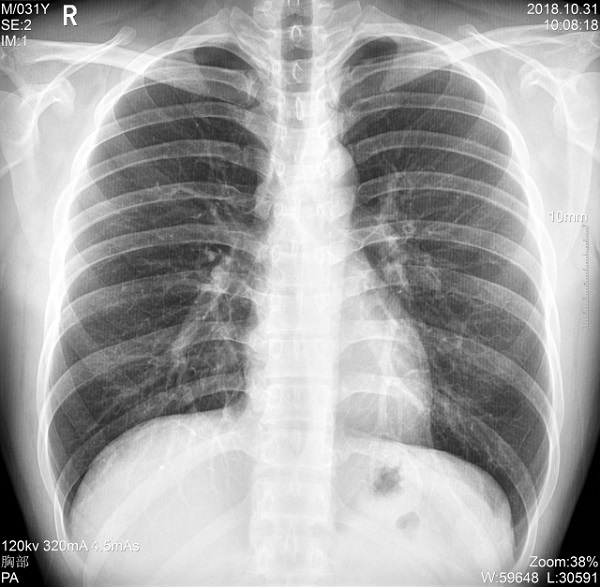

三、支持高千伏摄影 肺部纹理更有层次

PLX5500的最大可调千伏达到150kV,在达到一定高电压后,与骨骼相重叠的软组织或骨骼本身的细小结构及含气的管腔等,均可清晰显示。